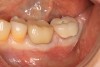

(15.) Clinical view of final individual crowns on Nos. 12 and 13.

Figure 15